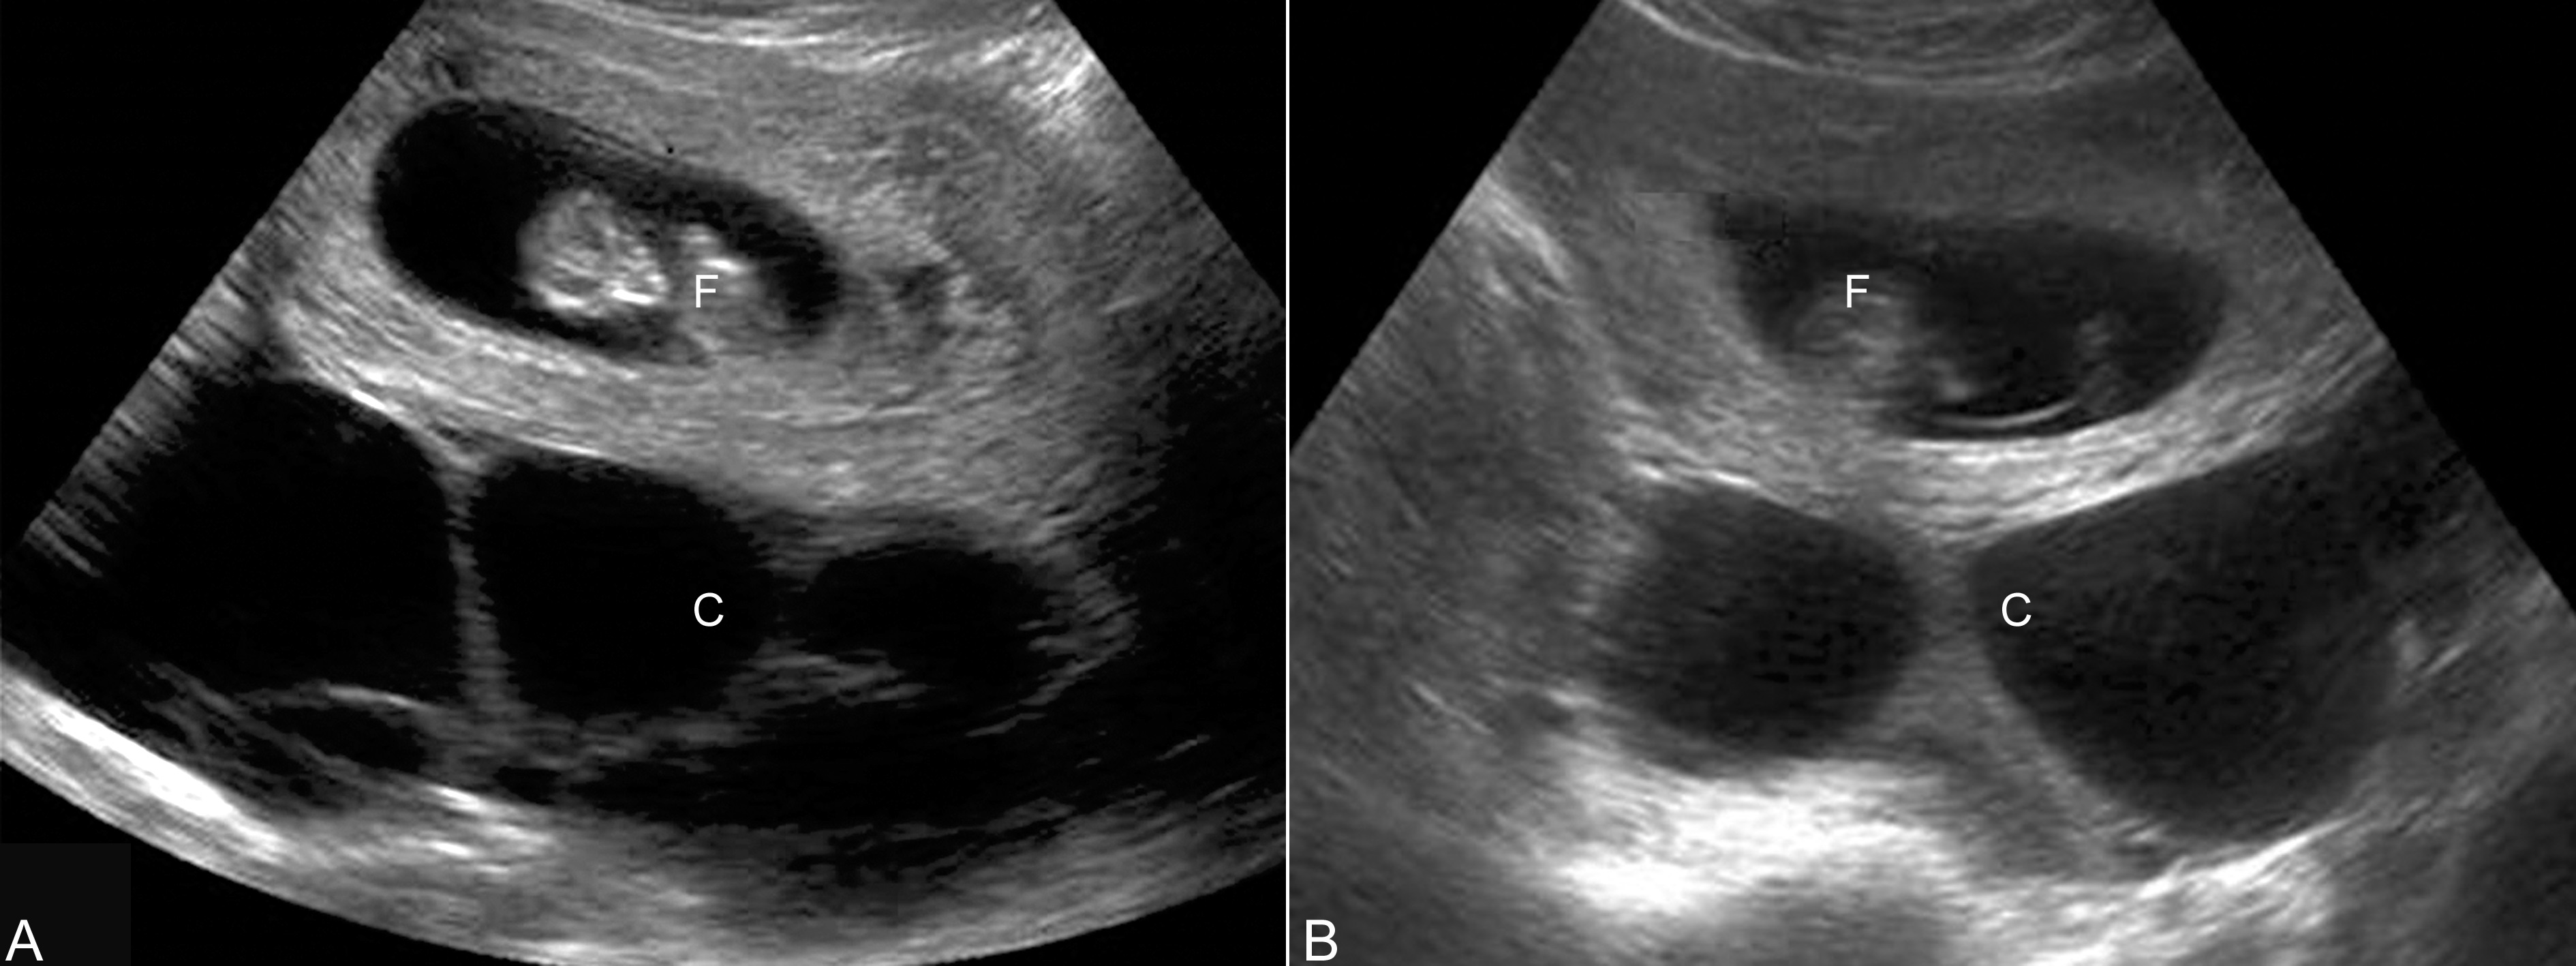

2.卵巢过度刺激 卵巢过度刺激(ovarian hyperstimulation)又称卵巢高反应状态,是辅助生殖技术中的常见现象,形成类似卵巢过度刺激综合征的改变。检查时可以显示卵巢明显增大,形态不规则,边缘清楚,内部可以显示大小不等的多房样无回声(图1),如果发现腹腔内或胸腔内有游离性无回声,应提示临床有卵巢过度刺激综合征(ovarian hyperstimulation syndrome)存在,结合临床表现可以做出诊断。卵巢过度刺激状态多会自行消失,部分病人可以持续到妊娠中期,并引发下腹部不适。

图1卵巢过度刺激声像图 10周妊娠,双侧卵巢可见多房性无回声,提示卵巢过度刺激